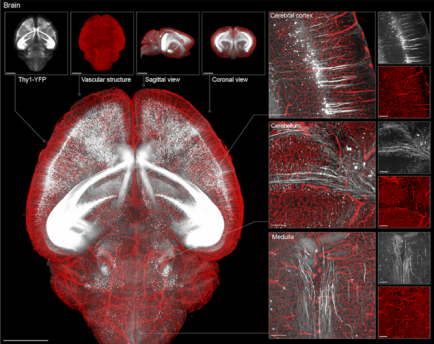

论文中展示了啮齿类、非人灵长类和人类脑组织经处理后,神经突触等亚细胞级精细结构在显微镜下均清晰可见。团队还发现,离子液体处理后的样本经荧光染料染色后,其信号强度可提升2到30倍。这些为跨尺度进行三维数据获取与空间重建奠定了坚实基础。

基于该项全球首创的技术,团队在国际上首次实现单神经元水平“输入—输出”的准确链接,为深入解析脑功能的神经环路机制提供了新的机遇。结合团队自主研发的重建算法,VIVIT技术还可构建从亚细胞到全器官的三维图谱,精准再现包括细胞器、神经突触在内的精细结构和位置,为各种器官绘制纳米级三维立体“画像”。